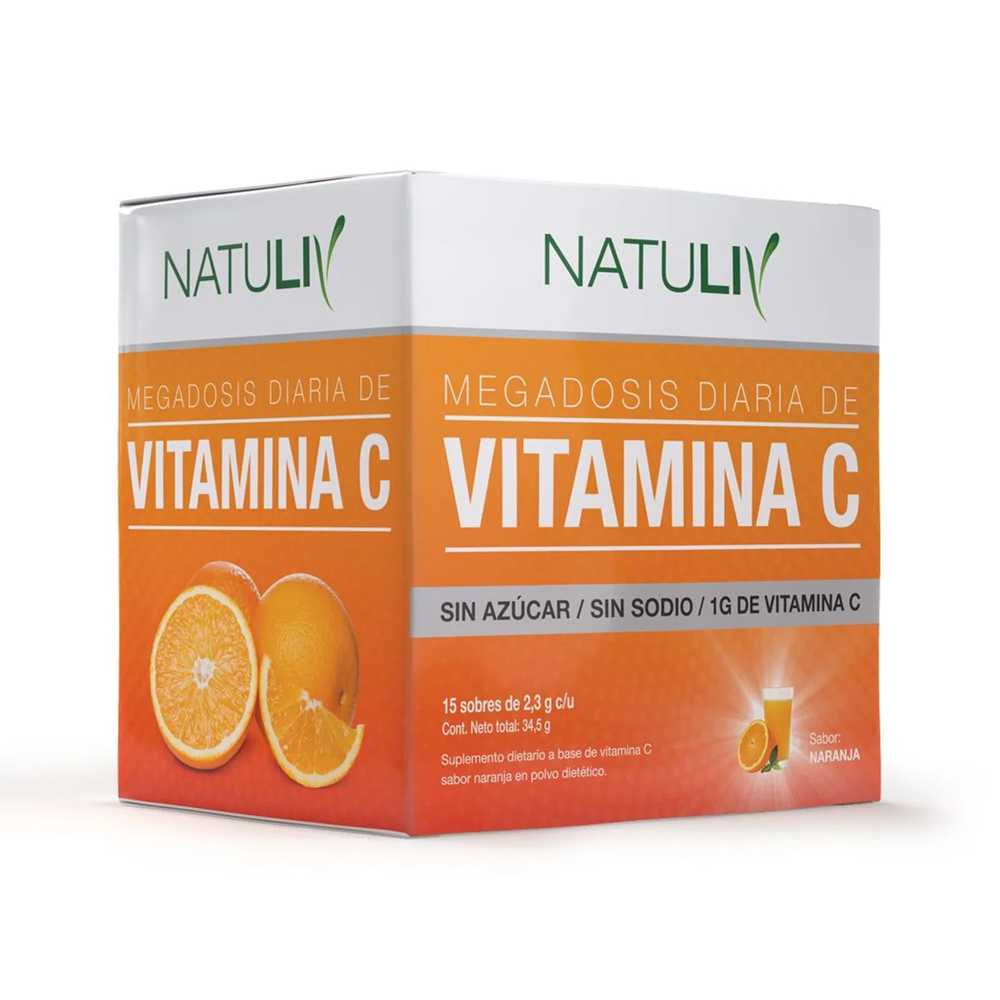

Vitamina C 15 sobres Natuliv

$6,300.00

La Vitamina C, o ácido ascórbico, es un potente antioxidante esencial para la salud, especialmente en la síntesis de colágeno y la protección celular. Este suplemento tiene múltiples beneficios, incluyendo la mejora de la cicatrización de heridas, la absorción de hierro, y el fortalecimiento del sistema inmunitario.

La Vitamina C, conocida científicamente como ácido ascórbico, es un potente antioxidante que juega un papel crucial en la salud general. Su capacidad para retrasar la oxidación de las moléculas la convierte en un aliado invaluable en la protección de nuestras células. Además, es fundamental en la síntesis de colágeno, el componente esencial para mantener la integridad de la piel, tendones, ligamentos, vasos sanguíneos, dientes y huesos. Por lo tanto, la salud de estos tejidos depende directamente de su consumo adecuado.

Presentacion

Suplemento deportivo en capsulas. 15 sobres. Sabor naranja. Libre de Gluten.

Beneficios

- Contribuye a la salud de los tejidos.

- Vital para la cicatrización de heridas.

- Potencia la absorción del hierro de origen vegetal.

- Favorece la síntesis de neurotransmisores.

- Regula el sistema inmunitario.

- Optimiza la recuperación post-entrenamiento.

- Previene infecciones urinarias.

- Reduce cansancio y fatiga.

Ingredientes

Vitamina C (Ácido Ascórbico).

Modo de uso

Se recomienda tomar 1 sobre disuelto en 220ml de agua.

Advertencias

Suplementa dietas insuficientes, consulte a su médico y/o nutricionista. No consumir en caso de embarazo, lactancia, ni en niños. Consumir este producto de acuerdo a las recomendaciones de ingesta diaria establecidas en el rótulo. El consumo de suplementos dietarios no reemplaza una dieta variada y equilibrada. Este producto está indicado para personas que realizan ejercicios físicos. Su consumo debe realizarse bajo control médico. Mantener en un lugar fresco y seco, fuera del alcance de los niños. No exponer a temperaturas mayores a 25oC.